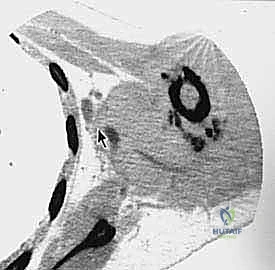

- التصوير الطبي المتقدم: استخدام الرنين المغناطيسي (MRI) لتقييم الأنسجة الرخوة، والأشعة المقطعية (CT scan) للصدر للبحث عن أي نقائل سرطانية (Metastasis)، والتصوير المقطعي بالإصدار البوزيتروني (PET Scan).

الخطوة 3: التعامل مع عظم الترقوة (Clavicle Osteotomy)

يتم كشف عظم الترقوة وقصه (قطعه) من المنتصف أو بالقرب من مفصل القص. هذه الخطوة "تفتح الباب" للوصول إلى الهياكل الحيوية العميقة.

الخطوة 4: السيطرة على الأوعية الدموية والأعصاب (الخطوة الأهم)